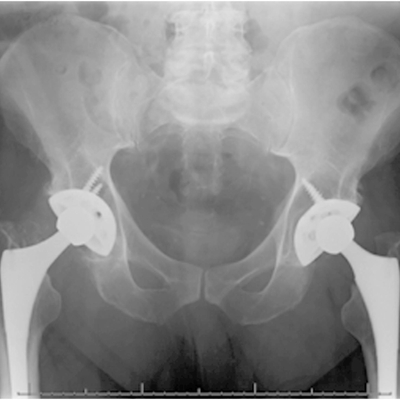

Click on an image below to view more info.